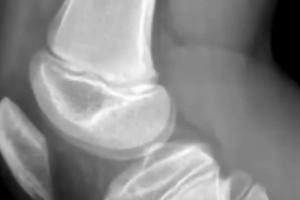

受伤孩子母亲张女士告诉荔枝新闻 ,他们老家在陕西西安,2024年2月特意带孩子前往大连加入“嗨球”青训,每天除去上学、写作业,训练时间至少4小时左右。在较高的强度之下,孩子膝盖受伤,有“胫骨结节炎、髌腱炎、骨裂”,教练的一些不当言语也给孩子造成心理伤害,因而产生退出的想法,却被索要高额赔偿才能换取“自由身”。